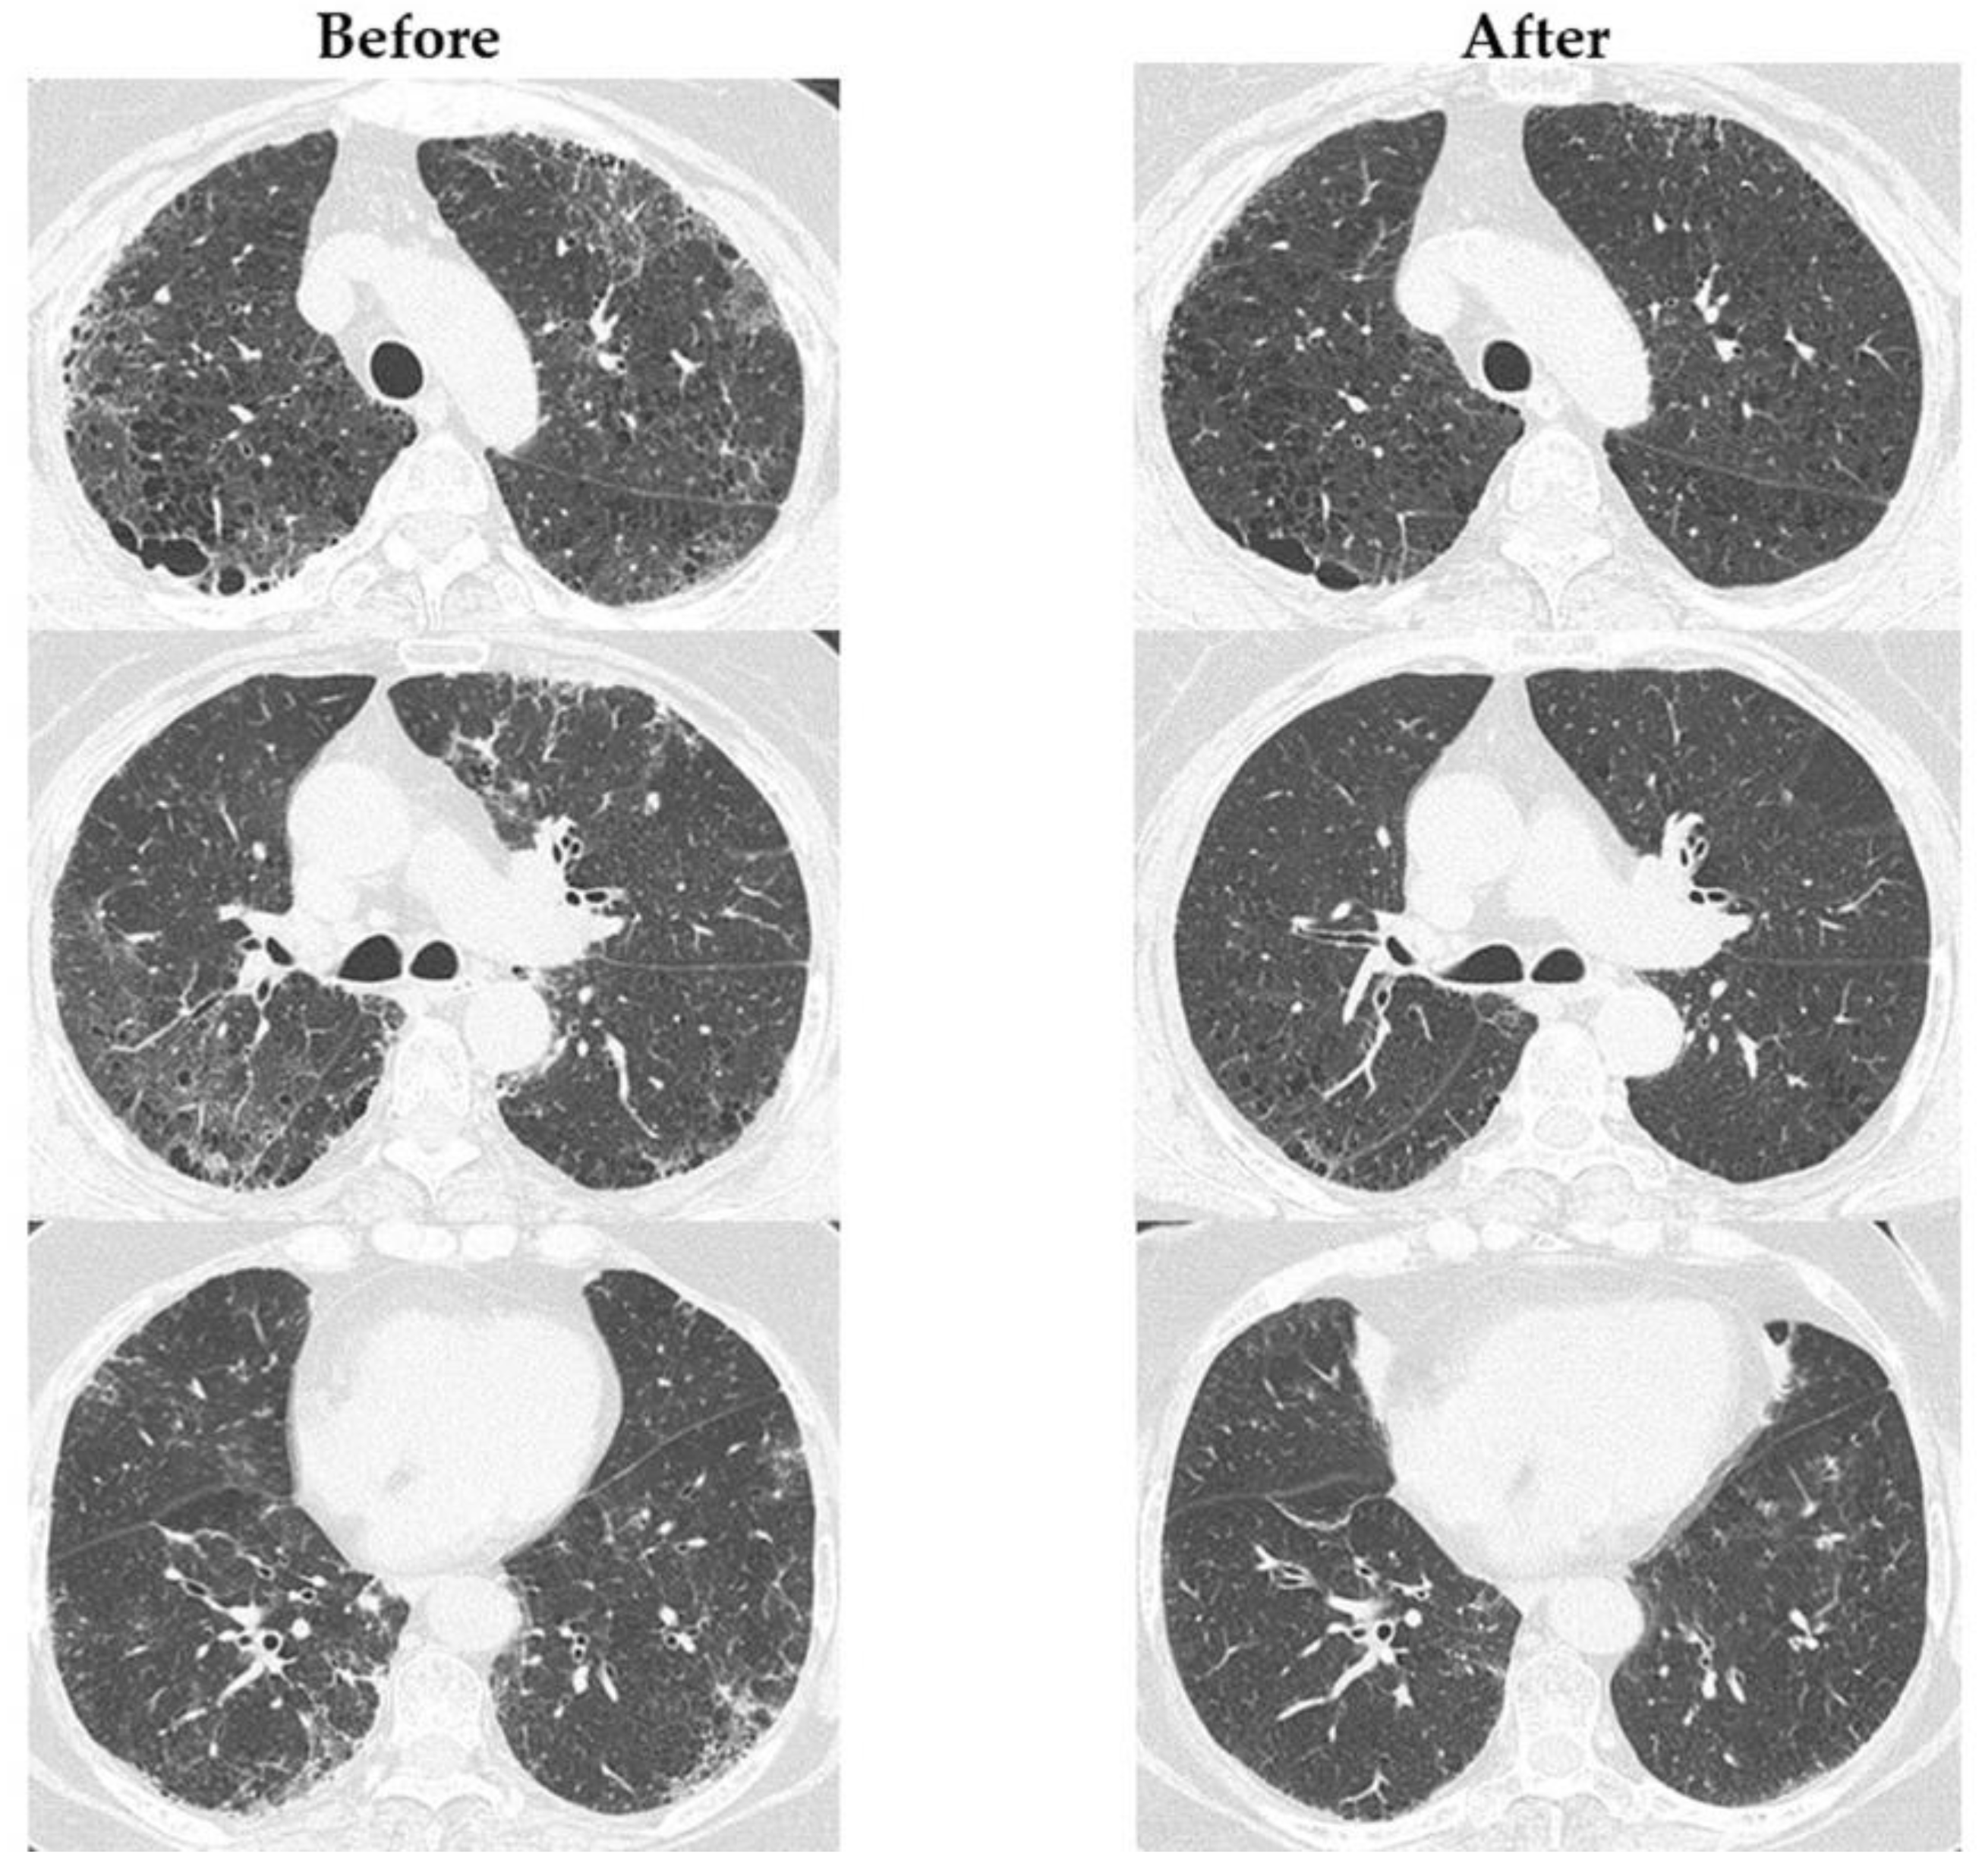

3.3. Therapeutic Effects of Abatacept in Patients with RA-ILD

Figure S1 shows the change in RA disease activity before and 1 year after the start of ABT administration. The following indicators were significantly improved after 1 year’s administration of ABT: DAS28CRP, 2.0 (range, 1.6–2.6); SDAI, 4.2 (range, 1.7–8.3); and CDAI, 3.9 (range, 1–7.8) (all p < 0.0001). Figure 1 shows the changes in ILD indicators before and 1 year after the start of ABT administration. The total GGO score (3.7 [range, 2.2–5.3]) was significantly decreased (p < 0.0001) after 1 year of ABT administration. Figure 2 shows the changes in chest HRCT scores, categorized by UIP-like and non-UIP-like patterns, before and 1 year after the start of ABT administration. The following values were significantly lower after 1 year of ABT administration: the total GGO score in the UIP-like pattern group (3.7 [range, 2.3–6.7], p = 0.008); the total GGO score in the non-UIP-like pattern group (3.6 [range, 1.8–5.1], p < 0.002); and the total fibrosis score in the UIP-like pattern group (4.3 [range, 3.3–7.3], p < 0.042). Figure S2 shows the changes in chest HRCT scores, categorized by MTX use, non-use, smoking, and non-smoking, before and 1 year after the start of ABT administration. There is no difference in the abatacept response between these categorized groups. Figure 3 shows an example case of changes in chest HRCT findings before and 1 year after the start of ABT administration.

Figure 3.

An example case of changes in chest HRCT findings before and 1 year after the start of ABT administration. The images were evaluated at three CT levels: the aortic arch, the left tracheal bifurcation, and 1 cm above the diaphragm. The extent of GGO, septal thickening, and honeycombing in each lung lobe (right upper lobe, middle lobe, lower lobe, left upper lobe, and left lower lobe) was semi-quantitatively assessed in the three images. The total GGO score improved from 11 to 5.33 points, and the total fibrosis score improved from 5.67 to 3.33 points. Before: before ABT administration; After: 1 year after the start of ABT administration; GGO: ground-glass opacity.